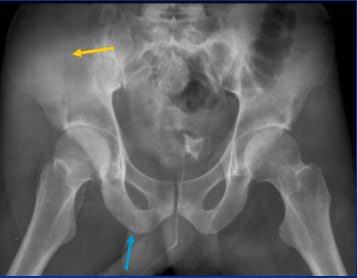

![]() |

| AP plain-film pelvic x-ray. Fractures involving right iliac wing (yellow arrow) and obturator ring (blue ring) are difficult to see despite good-quality AP film and exposure. All images courtesy of Dr. Craig Barnes. |